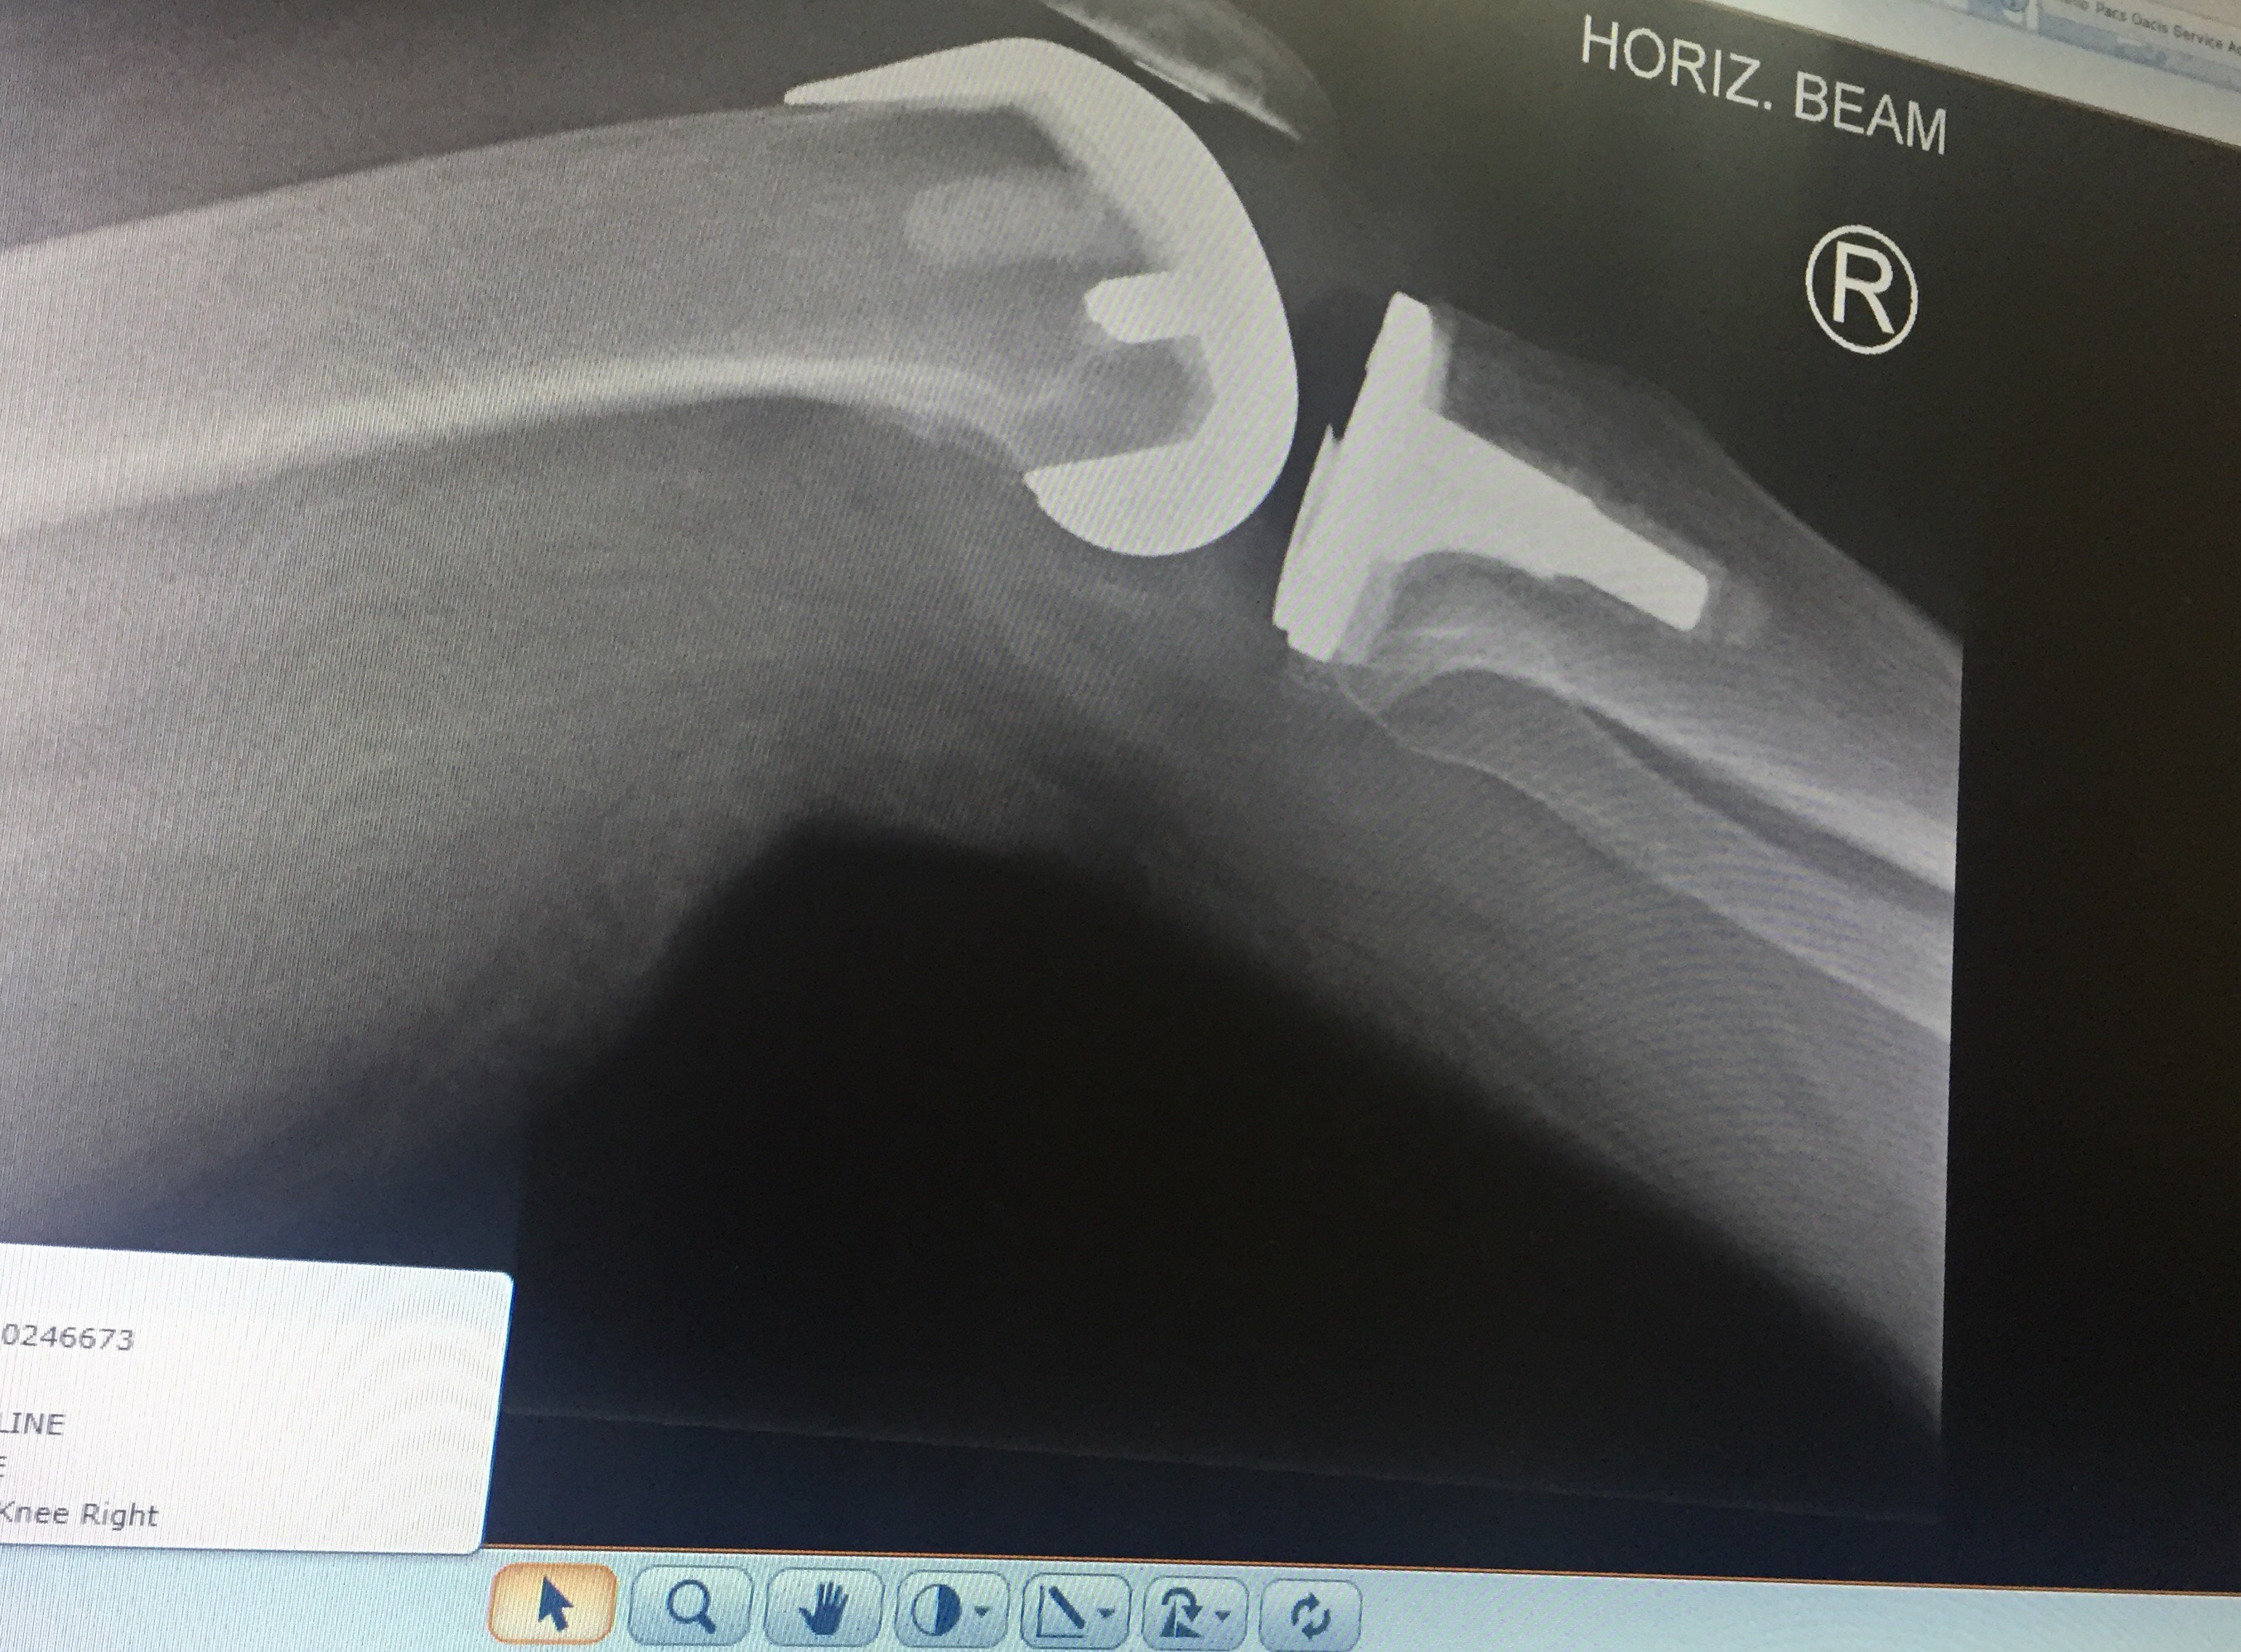

Graeme, my physio went onto his computer and showed me the results from the MRI I had at Flinders, and the Pet scan I had at the Royal Adelaide Hospital.

He read me the notes that were attached to each photo from the MRI and the Pet Scan, and I was able to photograph the MRI and the Pet Scan from the screen onto my iPhone.

This of course means that it is entirely possible that if I should need to have (as I do) another knee replacement, then the same thing could happen again, and I could have another stroke as a result of another knee replacement operation.

My left knee, the un-operated on knee, has rapidly become my “bad” knee, and so, unfortunately, such an operation is definitely “on the cards.”